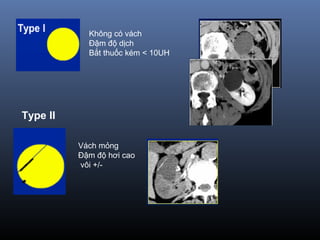

Phân lo i BosniakạType I Nang đ n thu nơ ầ :

Đ m đ d ch(-10-20 UH), đ ng d ng,gh rõ, không th y v ,không b tậ ộ ị ồ ạ ấ ỏ ắ

thu c c n quangố ả

=> Lành tính, không c n theo dõiầ

Type II Nang không đi n hìnhể :

vài vách m ng, vài đ m vôi v , đ m đ d ch cao(> 50UH)ỏ ố ở ỏ ậ ộ ị

Không b t thu c c n quang (<10UH)ắ ố ả

=> Lành tính , không c n theo dõiầ

Không có vách

Bắt thuốc kém < 10UH

Đậm độ dịch

Type II

Vách mỏng

Đậm độ hơi cao

vôi +/-